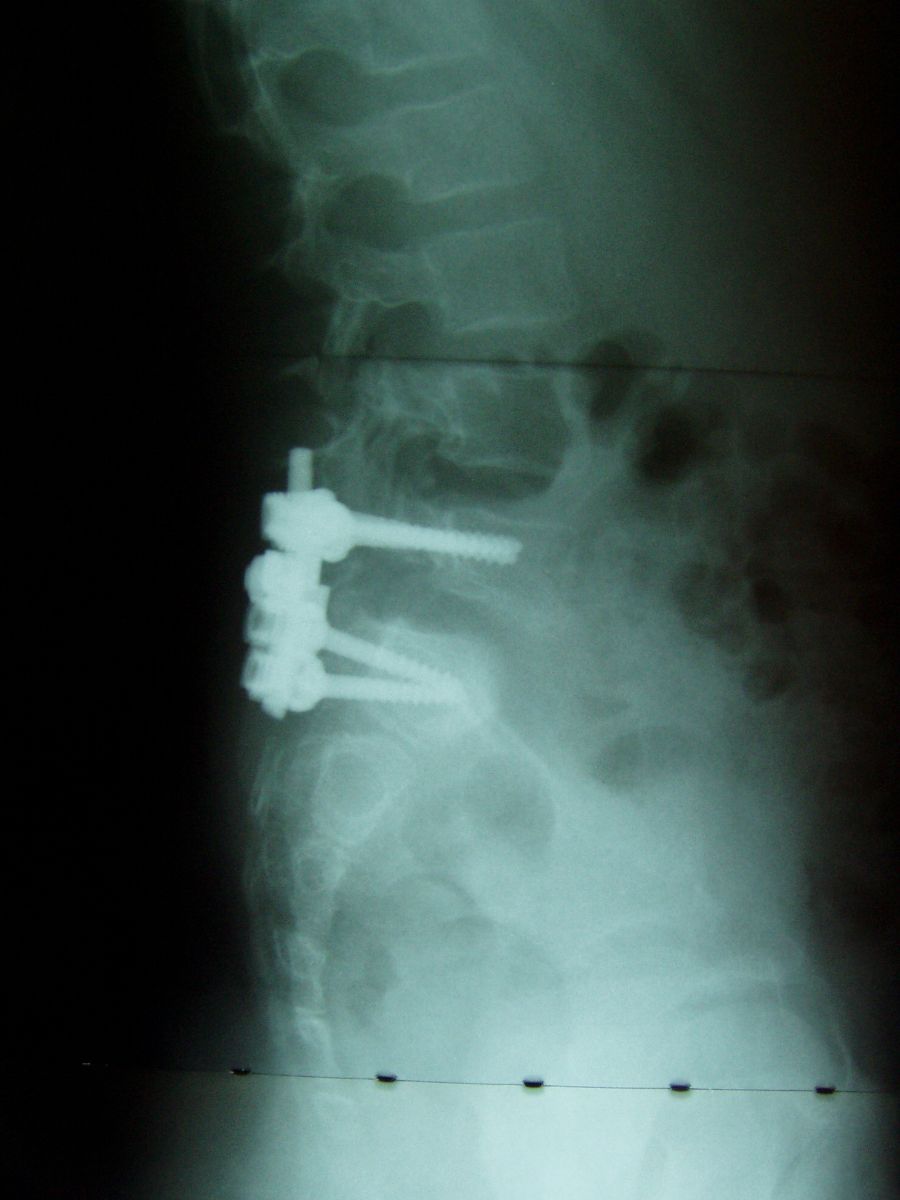

Hasta 7 yaşımda ameliyat edildi ve kemik köprüler oluşturmak amacı ile kemik aşısı yapılarak vida ile tespit uygulandı.

Hastanın ameliyat sonrası görüntüsü.